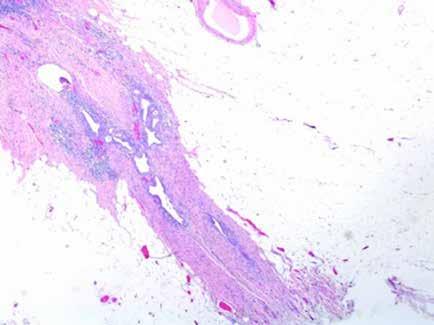

Se realiza medulograma, con el diagnóstico de síndrome mielodisplásico con displasia unilínea (megacariocítica) e hipoplasia eritroide. Asimismo, destaca vacuolización en precursores mieloides y eritroide (Figura 2), motivo por el que se solicita estudio molecular en médula ósea dirigido a estudio de mutaciones en el gen UBA1.

Las vacuolas son el hallazgo morfológico característico de esta patología, pudiendo observarse en médula ósea en los precursores mieloides y eritroides. Sin embargo, la presencia de vacuolas es un dato inespecífico que puede observarse en distintas situaciones: intoxicación por alcohol, déficit de zinc o cobre, neoplasias mieloides. Tampoco, se considera una alteración morfológica sugestiva de displasia. Según un reciente estudio retrospectivo publicado por Lacombe et al, la presencia de 10% o más precursores mieloides con más de una vacuola se asocia a síndrome de VEXAS con alta sensibilidad y especificidad (2,3).